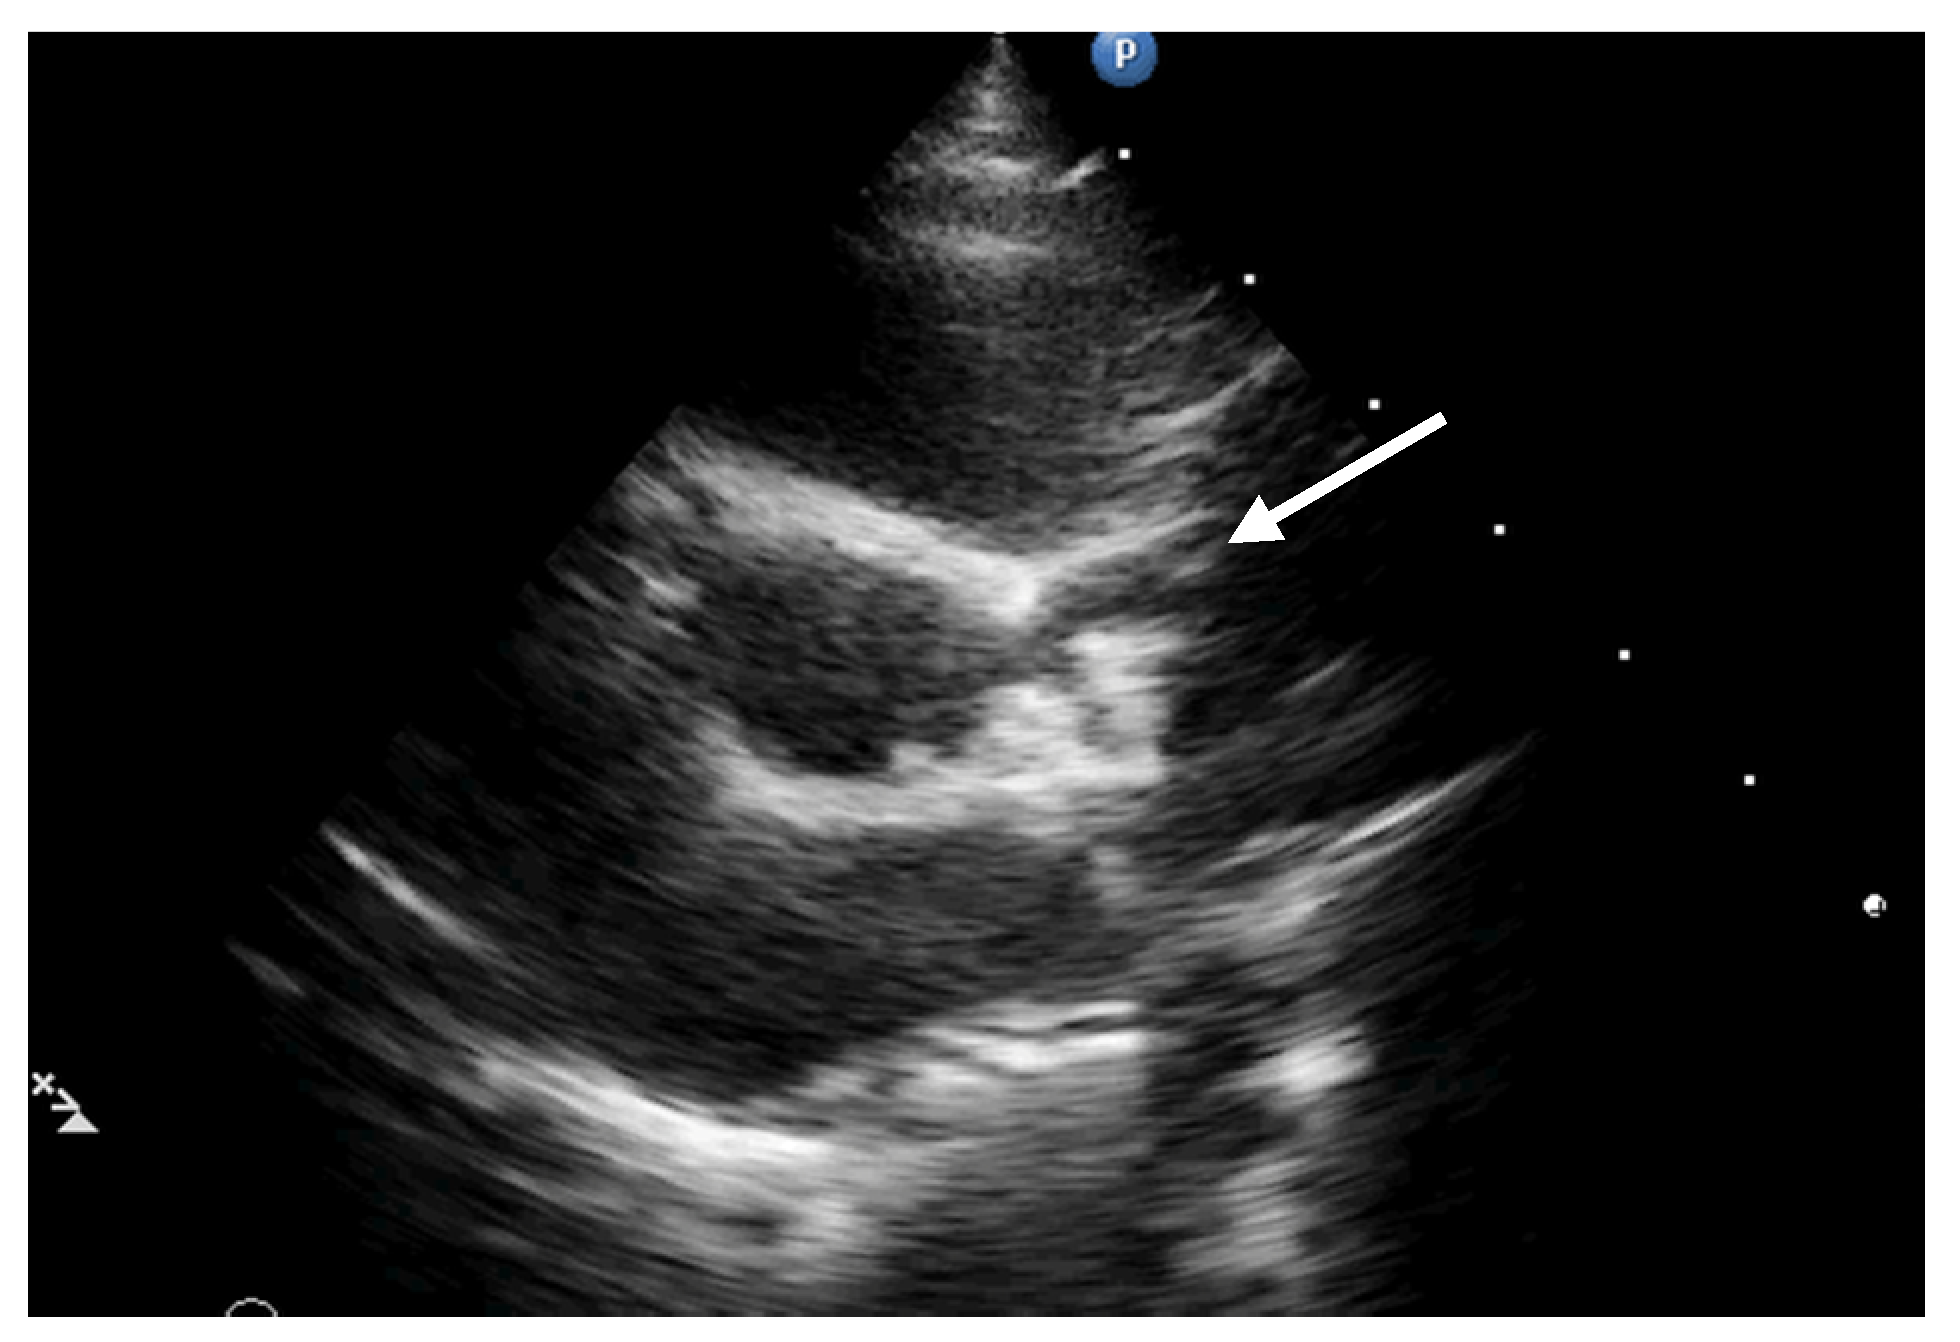

2. Case Report